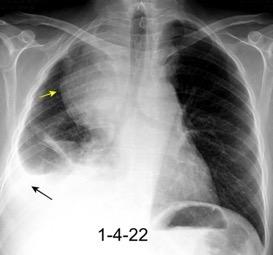

Síndrome de afectación postcardiaca (postcardiac injury)

Post infarto 1-7 % (Dressler)

Trauma cerrado Implantación marcapasos

Cirugía cardiaca. 17-31% (Post.pericardiotomía)

3707 pacientes 29 Derrames (0,78%) > de 25% del hemitórax

Todas menos 2 Izdos.

Angioplastia

By-pass coronario 21-10-03